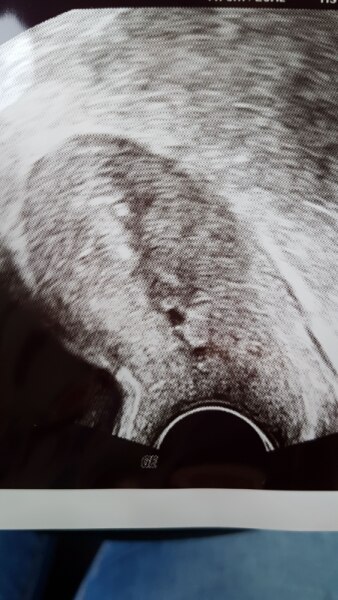

Ja... sieht sehr nach fg aus. Sie hat mir die Wahl gelassen auf die blutung zu warten oder AS. Ich warte nun... Die fruchthöhle is wohl kleiner geworden und nach unten gerutscht. Hänge mal das Bild an... Bin echt traurig. Nun ab ich vor jedem Kind eine fg! :'(

Da ist es...

Bild zu